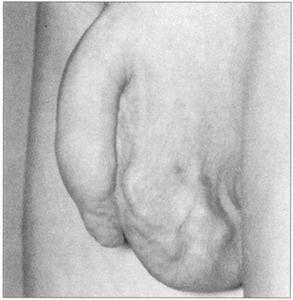

精索静脉曲张的患者(图215)通常会有阴囊上部的肿胀(95%为左侧)。虽然患者通常没有症状,但有时会引起轻微的疼痛。精索静脉曲张很受重视,因为其与不育有关。

图215 精索静脉曲张